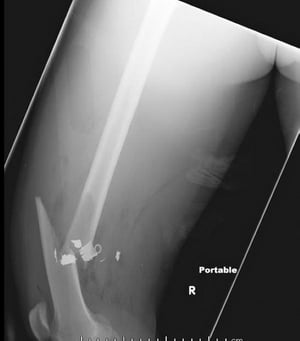

대퇴골 원위부의 나선형 골절

이미지

살아있는 예술 기업/과학 사진 라이브러리

X-ray에서 골절의 모양은 다음 용어를 사용하여 비교적 정확하게 설명할 수 있습니다.